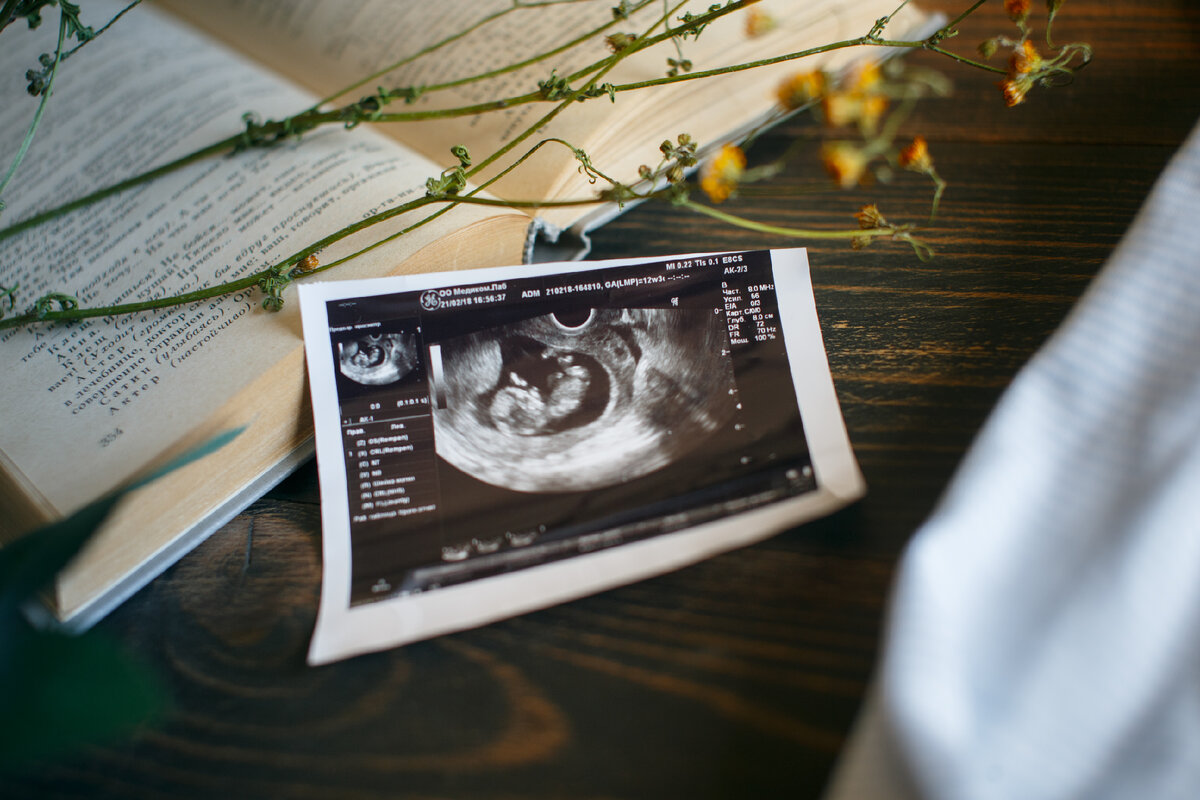

Забеременев, я чувствовала себя прекрасно. У меня не было токсикоза, я порхала как бабочка, очень много гуляла на свежем воздухе, мечтала поскорее обнять своего малыша. Правда, у меня не было аппетита и к 8-ми месяцам беременности я набрала всего 5 кг и еще 2кг на последнем месяце. Но мое счастье омрачили слова врача на втором скрининге-УЗИ. Этот диагноз, словно гром среди ясного неба, очень сильно подкосил меня… Я рухнула на землю, все вокруг поплыло, а в голове эхом отдавались слова врача “похоже, что у вас расщелина… расщелина губы… возможно и расщелина неба…” Фото из личного архива.

Забеременев, я чувствовала себя прекрасно. У меня не было токсикоза, я порхала как бабочка, очень много гуляла на свежем воздухе, мечтала поскорее обнять своего малыша. Правда, у меня не было аппетита и к 8-ми месяцам беременности я набрала всего 5 кг и еще 2кг на последнем месяце. Но мое счастье омрачили слова врача на втором скрининге-УЗИ. Этот диагноз, словно гром среди ясного неба, очень сильно подкосил меня… Я рухнула на землю, все вокруг поплыло, а в голове эхом отдавались слова врача “похоже, что у вас расщелина… расщелина губы… возможно и расщелина неба…”

Фото из личного архива.